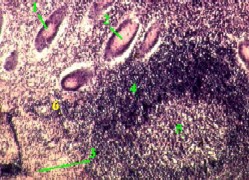

II. Большое увеличение: слизистая оболочка и подслизистая основа

1,в-г. Препарат - толстая кишка. Окраска гематоксилин-эозином.

1. Здесь при большем увеличении представлены крипты (1.А).

а) А. В выстилающем их эпителии преобладают слизеобразующие бокаловидные клетки (1.Б) - светлые и округлые.

Б. Поэтому данные крипты с гораздо большим основанием (чем крипты тонкого кишечника) можно называть железами.

б) Среди остальных клеток эпителия (с тёмной цитоплазмой) основную массу составляют столбчатые клетки (1.В).

2. Узкие прослойки соединительной ткани между криптами образуют, как мы знаем, собственную пластинку (2) слизистой оболочки.

3. Ещё глубже располагаются

мышечная пластинка (3) слизистой оболочки и

подслизистая основа (II) с сосудами (5).